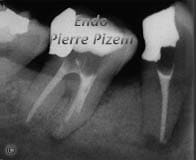

Il y a 7 ans, on a suggéré à cette patiente d'extraire cette prémolaire, car le pronostic de ladite dent était mauvais. Vu le pronostic douteux, la solution politiquement raisonnable et prudente était de remplacer cette dent par une couronne sur implant. Le manque de tissu périradiculaire impliquait une régénération tissulaire guidée qui impliquait elle-même un curetage. La proximité du foramen mentonnier de celle du site à cureter comportait un risque de paresthésie permanente associé à cette intervention. Cela en soi avait déjà un rien d'inquiétant. Ajoutez-y aussi un risque possible de rejet du greffon et l'on obtient une patiente qui cherche avidement un deuxième avis.

À l'examen clinique je note une fistule ouverte au buccal et un degré de mobilité de la dent comprise entre un et deux millimètre, en cas de reprise de traitement, la traction de la digue sur le crampon allait-elle à elle seule extraire la dent que je tentais de sauver?

L'examen radiologique révèle toutefois, d'un point de vue strictement prothétique une dent parfaitement restaurable, d'un point de vue parodontal une perte osseuse en table de quelques millimètres et d'un point de vue endodontique une très large lésion aux bords circonscrits dont l'origine provient d'une contamination récurrente du système canalaire.

Le raisonnement fut le suivant: tenter de sauver cette dent en la retraitant endodontiquement. Dans le pire des cas la dent n'aura pas pu être sauvée, mais les fréquents changements d'hydroxyde de calcium auront non seulement eu une activité antibactérienne, mais ils auront aussi permis la neutralisation des endotoxines à l'origine de l'inflammation. En agissant ainsi il est possible d'espérer une régénération des tissus périradiculaire à proximité du nerf mentonnier.

En toute connaissance de cause, la patiente a accepté de tenter de sauver sa dent. Celle-ci a dû être patiente et persévérer, plusieurs changements d'hydroxyde de calcium ont été nécessaires. Les résultats ont toutefois été encourageants dés le départ, car 8 jours après la première insertion d'hydroxyde de calcium, la fistule avait disparu. Dans les mois qui suivirent les clichés radiologiques ont progressivement permis de constater régénération complète des tissus périradiculaires.